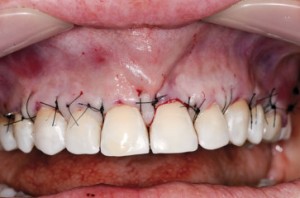

| Zabieg pokrycia recesji w okolicy zębów 16-26 dwoma przeszczepami tkanki łącznej. Przed zabiegiem odbudowano CEJ w tych zębach, w których doszło do jego zniszczenia |

||